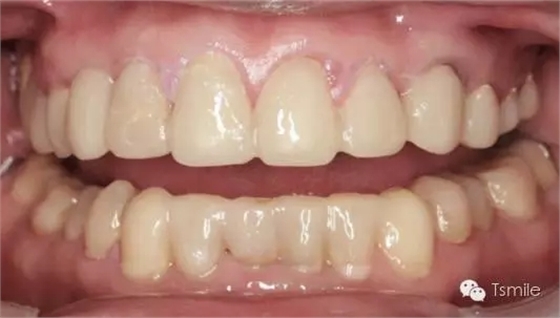

例如面對一個牙列重度磨耗的美學(xué)修復(fù)患者,我們首先根據(jù)患者主訴和美學(xué)檢查形成美學(xué)設(shè)計,然后通過數(shù)碼圖像表達(dá)美學(xué)設(shè)計思想,制作診斷蠟型,口內(nèi)制作診斷飾面,更加真實(shí)地表達(dá)美學(xué)設(shè)計。根據(jù)患者的要求和口內(nèi)試戴情況調(diào)改診斷飾面,最終確定美學(xué)修復(fù)設(shè)計,即最終修復(fù)體的各種美學(xué)參數(shù)。接下來就是美學(xué)實(shí)現(xiàn)過程,在診斷飾面上進(jìn)行精確地牙體預(yù)備,制取印模和工作模型,技師按照最終診斷飾面的形態(tài)、大小和排列制作最終美學(xué)修復(fù)體,最后完成修復(fù)體粘接。

前兩個美學(xué)分析和美學(xué)表達(dá)過程已經(jīng)確定了患者滿意的最終的美學(xué)修復(fù)設(shè)計,也就是已經(jīng)確定了最終修復(fù)體的形態(tài)、大小、排列、牙齦曲線等各種美學(xué)參數(shù),美學(xué)實(shí)現(xiàn)就是復(fù)制前面已經(jīng)確定的美學(xué)設(shè)計的過程,包括牙體預(yù)備、印模制取、修復(fù)體制作、修復(fù)體試戴粘接等過程。